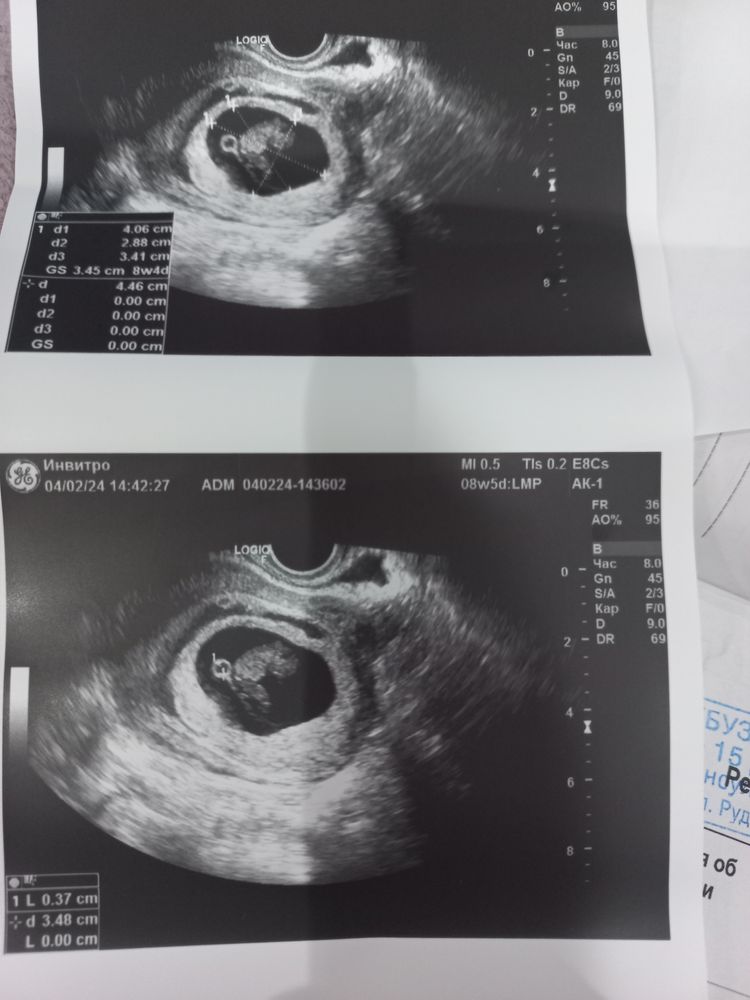

Сегодня была на узи. Под плодом виднеется что то кольцевидной формы . Что это не пояснили , просто сказали что нужно наблюдать. У кого такое было ?поделитесь пожалуйста своим опытом

нормальная картина на узи у вас, все прекрасно, в выписке найдите размеры жм